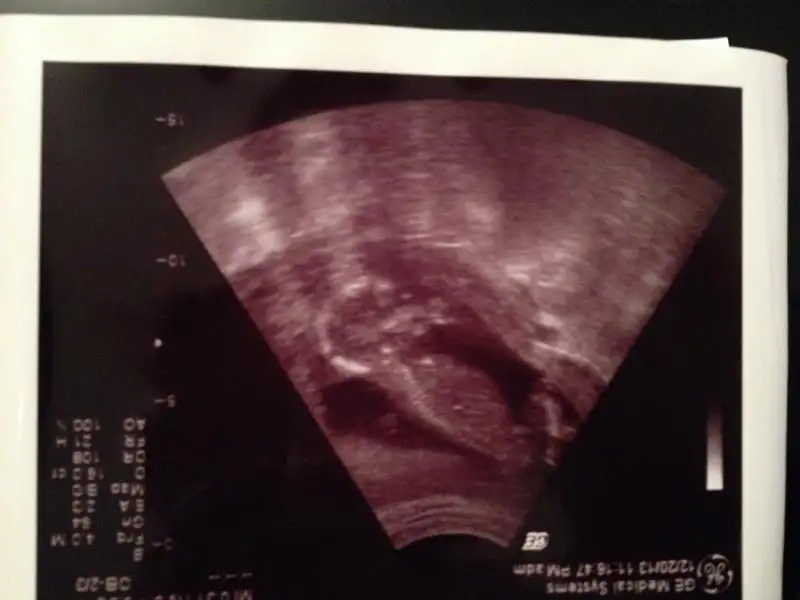

dr soylemeden siz gorun genital nub teorisi ( bebegin cinsiyeti)

Canim emin olmadiklarima demek istemiyrm ama sende pipi gibi gorunen bisi var ama o bacagida olabilir buyuk ihtimal kizsa eger nubu gorunmuyo

Teşekkürler yorumun için canım bende gördüm çıkıntıyı hatta yükleyemediğm fotolarda daha belirgin ama 13 haftalıkken bu kadar belirgin ve büyük pipi olurmu benim hala kızdan yana umudum var doktor bile erkeğe benziyor desede lütfen biraz daha yorum yazarmısın

zeynep 341 de yeni foto yükledim bunlara da bakar mısın yorum yapan arkadaşlar erkek dediler ama nedense hala kızdan yana umudum var yeşerip yeşerip duruyor gönlümden böyle geçtiği için mi acaba elbette her zaman hayırlısını diliyorum

bir daha bakıp yorumlar mısın lütfen